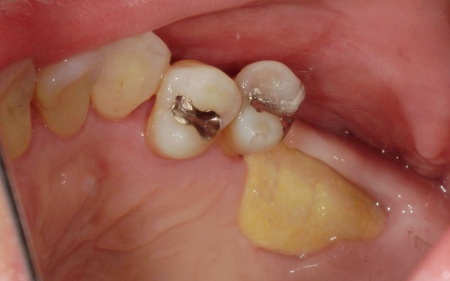

また、右下奥歯には、両隣の歯を土台にして橋を渡すように欠損部を補う被せ物「ブリッジ」が装着されていました。

右下奥歯は2本欠損しており、親知らず(第3大臼歯)と手前の奥歯(第2小臼歯)の2本でブリッジを支えていますが、これは親知らずに過度な負荷がかかる構造です。

親知らずはすでに大きく傾いており、こちらも温存が難しいため、ブリッジを除去してから親知らずを抜く必要があります。

次に、右下に装着されているブリッジを除去してから右下の親知らずを抜き、欠損部(第1大臼歯、第2大臼歯の部分)にインプラントを埋入しました。

また、右下の手前にある奥歯2本(第1小臼歯、第2小臼歯)は、新しく詰め物を作製して噛み合わせと見た目を整えています。